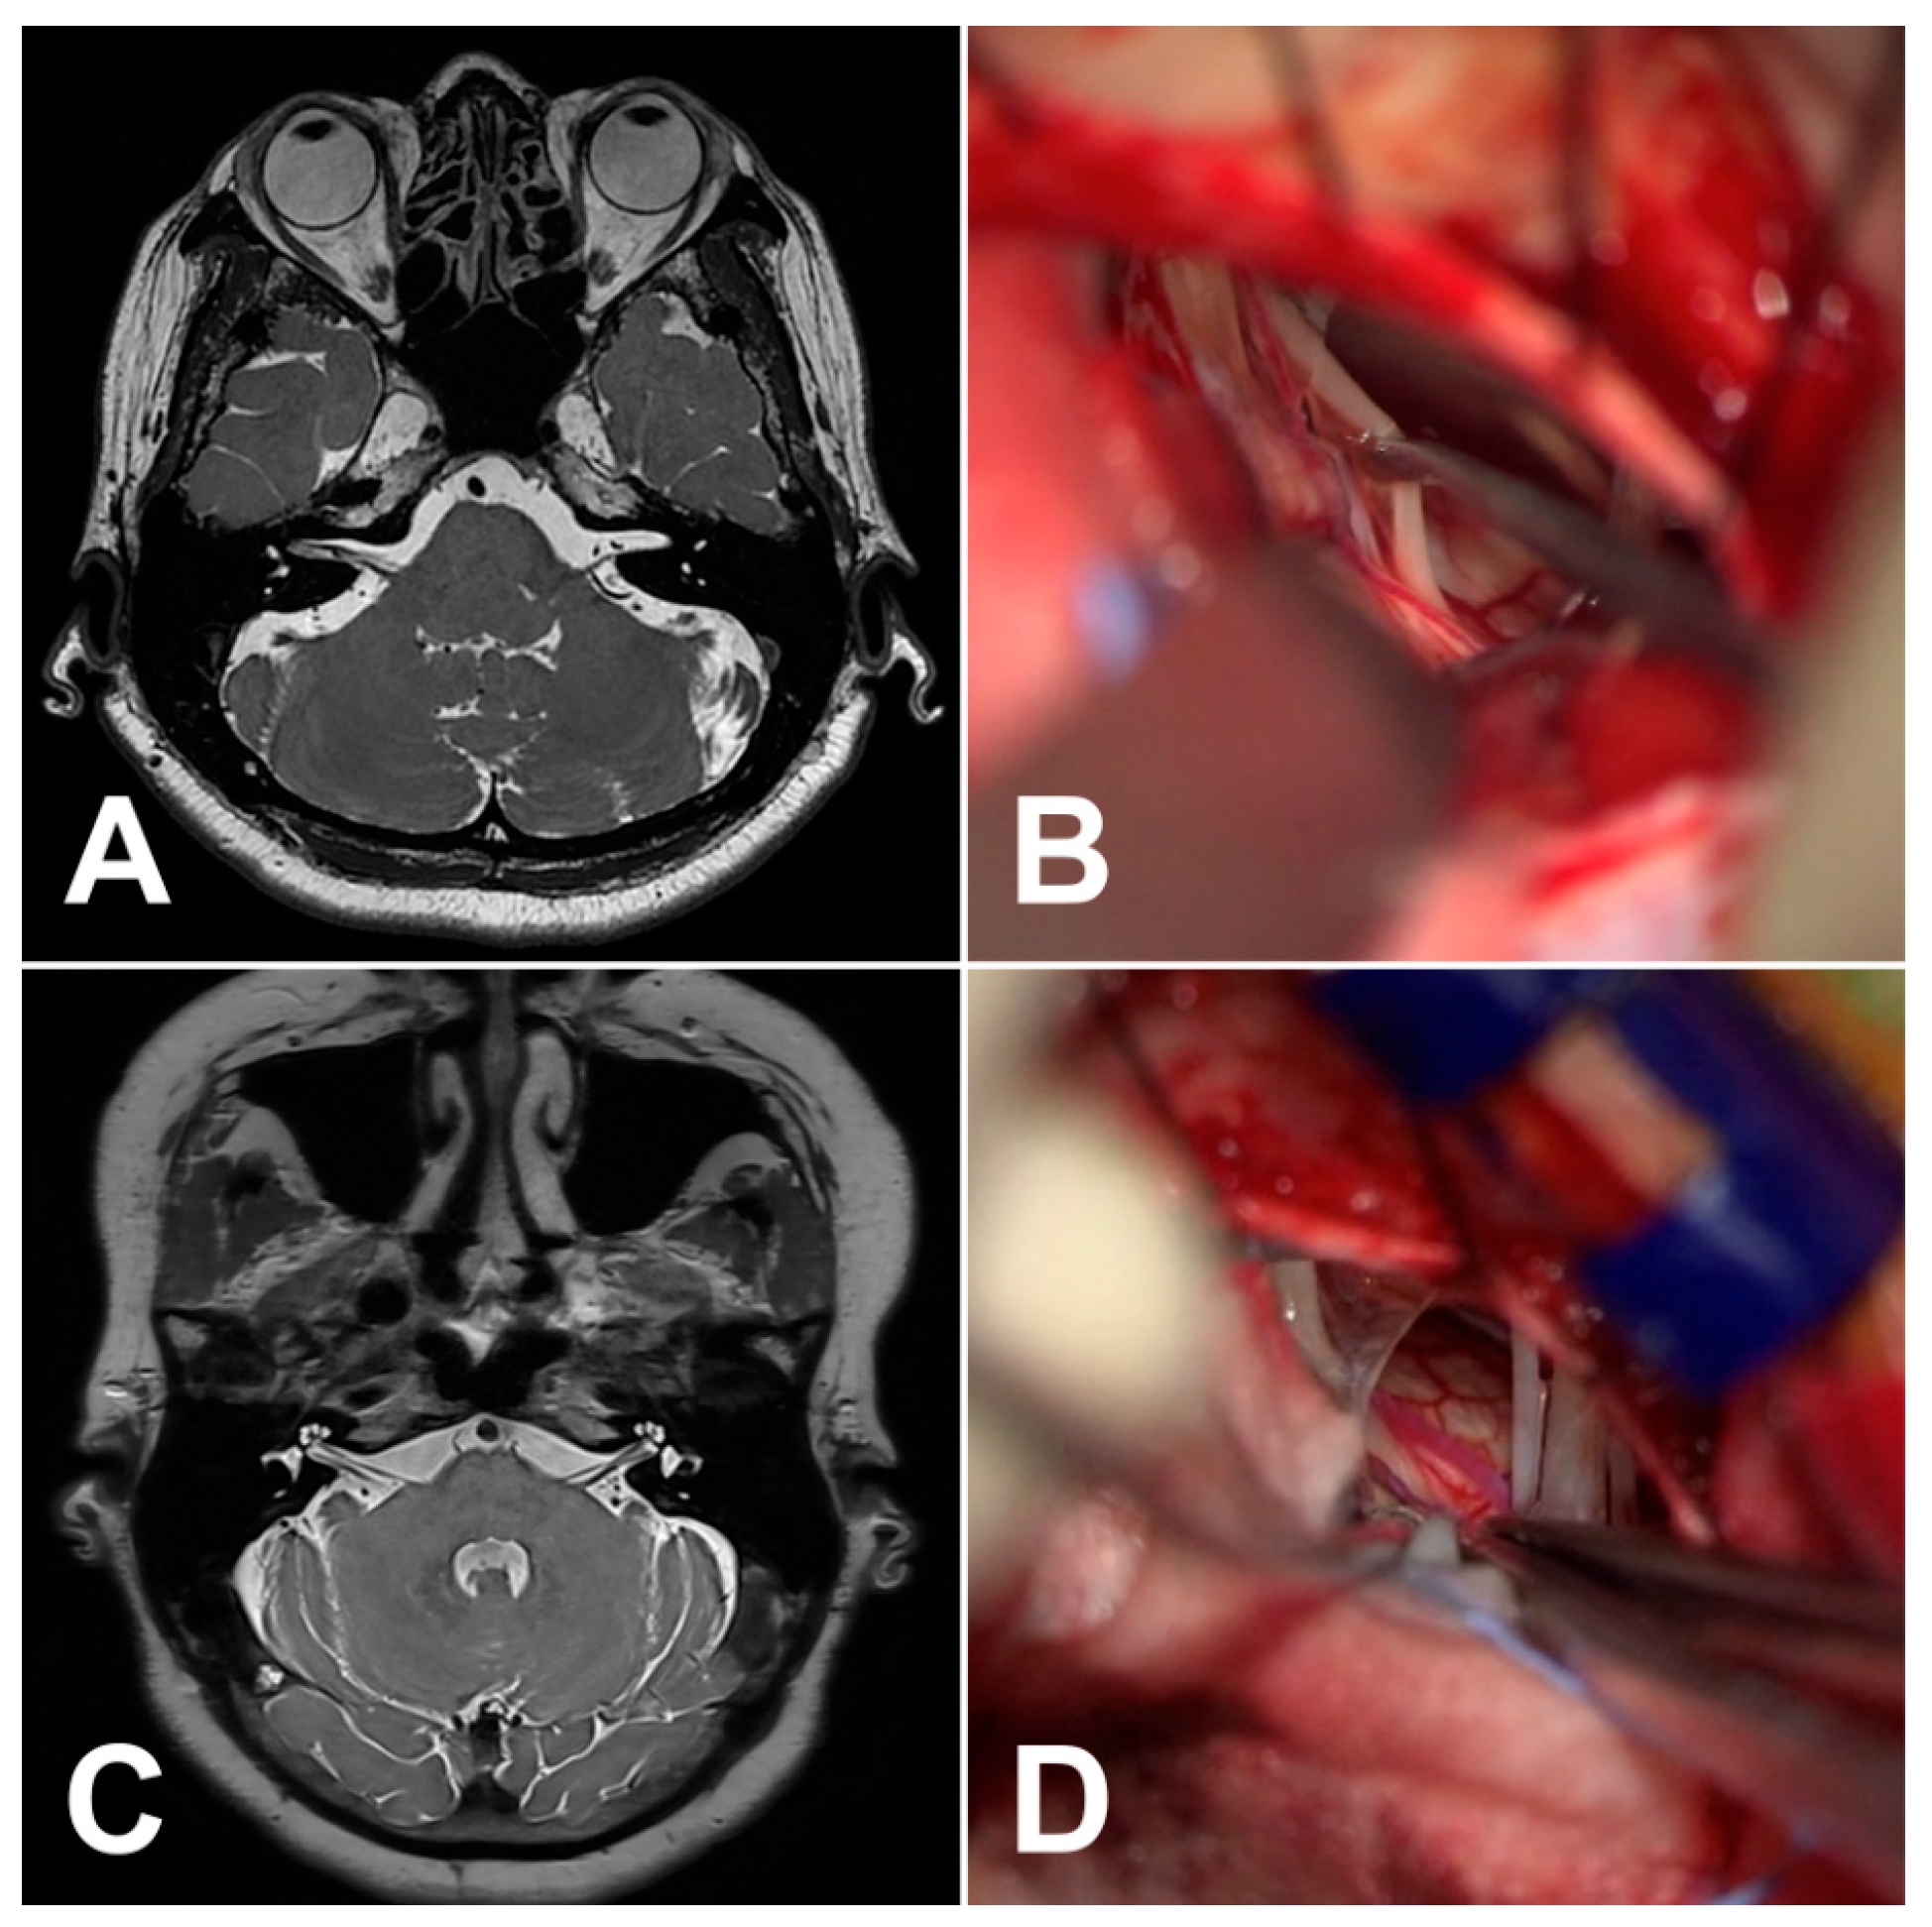

| Case No. | Age (Years, Sex) | Side | Symptom Duration | Offending Vessel | Compression Site | Compression Type | Outcome | Recurrence | Complication | FU |

|---|---|---|---|---|---|---|---|---|---|---|

| 1 | 44, F | Left | 24 | Arteriole | Cisternal (distal) | Arachnoid | Partial | No | No | 60 |

| 2 | 69, F | Left | 240 | AICA | Cisternal | Arachnoid | Complete | No | Transient facial palsy (HB Gr3) | 12 |

| 3 | 71, F | Right | 36 | AICA | Cisternal | Arachnoid | Complete | Yes | No | 56 |

| 4 | 48, F | Left | 38 | Vein | Cisternal | NA | Complete | No | Transient facial palsy (HB Gr3) | 40 |

| 5 | 56, F | Left | 40 | Arteriole | Cisternal | Arachnoid | Complete | No | No | 12 |

| 6 | 58, M | Left | 32 | Arteriole | Cisternal | Arachnoid | Complete | No | No | 12 |

| 7 | 58, M | Left | 6 | Vein | REZ | NA | Complete | No | Transient facial palsy (HB Gr3) | 12 |

| 8 | 70, F | Right | 12 | AICA | REZ (medial) | Arachnoid | Complete | No | No | 12 |

| 9 | 55, F | Left | 4 | AICA | Cisternal (medial) | Perforator | Complete | No | No | 12 |

| 10 | 64, F | Left | 84 | Arteriole | Cisternal (medial) | Loop | Partial | No | No | 6 |

| 11 | 53, F | Left | 36 | AICA | Cisternal | Perforator | Complete | No | No | 12 |

| 12 | 62, F | Left | 60 | AICA | REZ (medial) | Perforator | Complete | No | No | 24 |

| 13 | 68, F | Left | 24 | AICA | Cisternal (between CN VII and CN VIII) | Perforator | Complete | No | Transient facial palsy (HB Gr4) | 24 |

| 14 | 63, F | Left | 84 | PICA (small branch) + vein | REZ + cisternal | Sandwich | Complete | No | No | 24 |

| 15 | 62, F | Right | 240 | Arteriole + vein | Cisternal | Sandwich | Complete | No | No | 12 |

| 16 | 57, F | Right | 72 | AICA | Cisternal (distal) | Arachnoid | Complete | No | No | 12 |